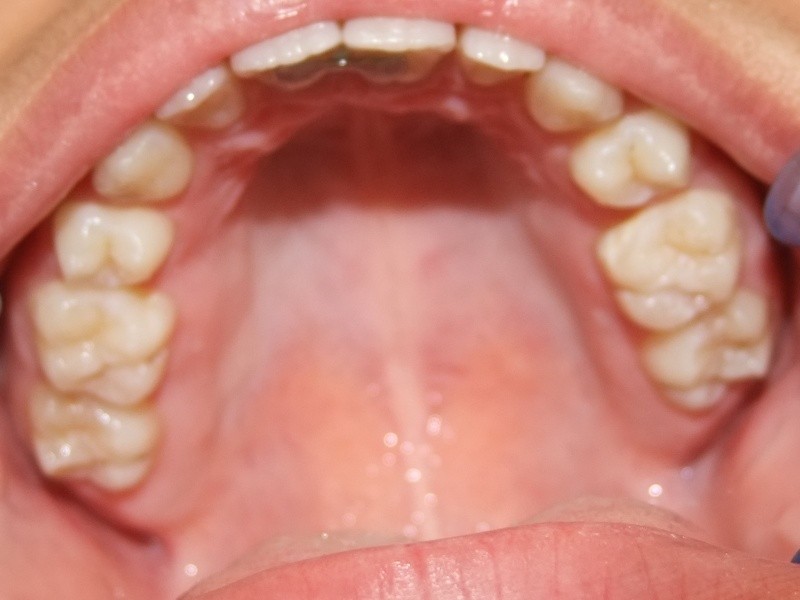

Na behandeling